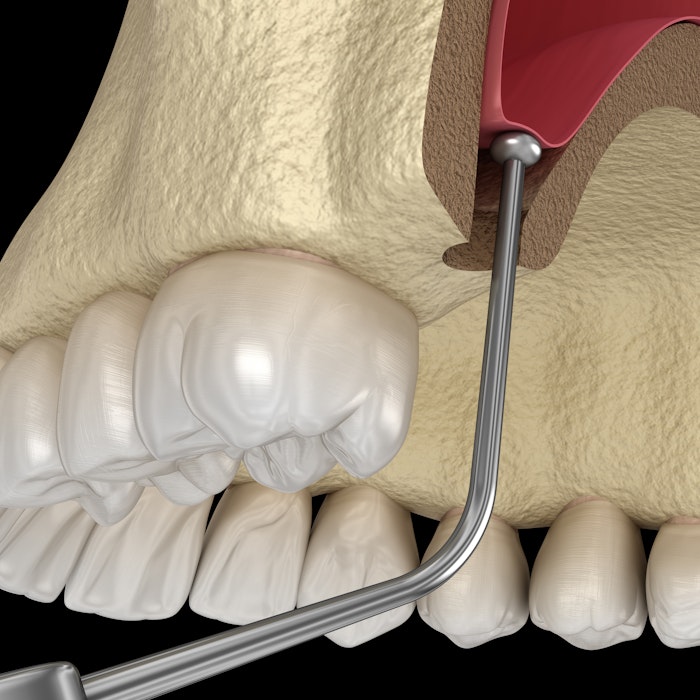

Take a Look at How Dental Implants Work

Dental implant treatment uses three components:

- A titanium implant integrates with your jawbone tissue to replace missing tooth roots.

- An abutment piece sits atop the implant.

- An implant-supported restoration connects to the abutment.

It typically takes three visits to our Orland Park office to complete the process.